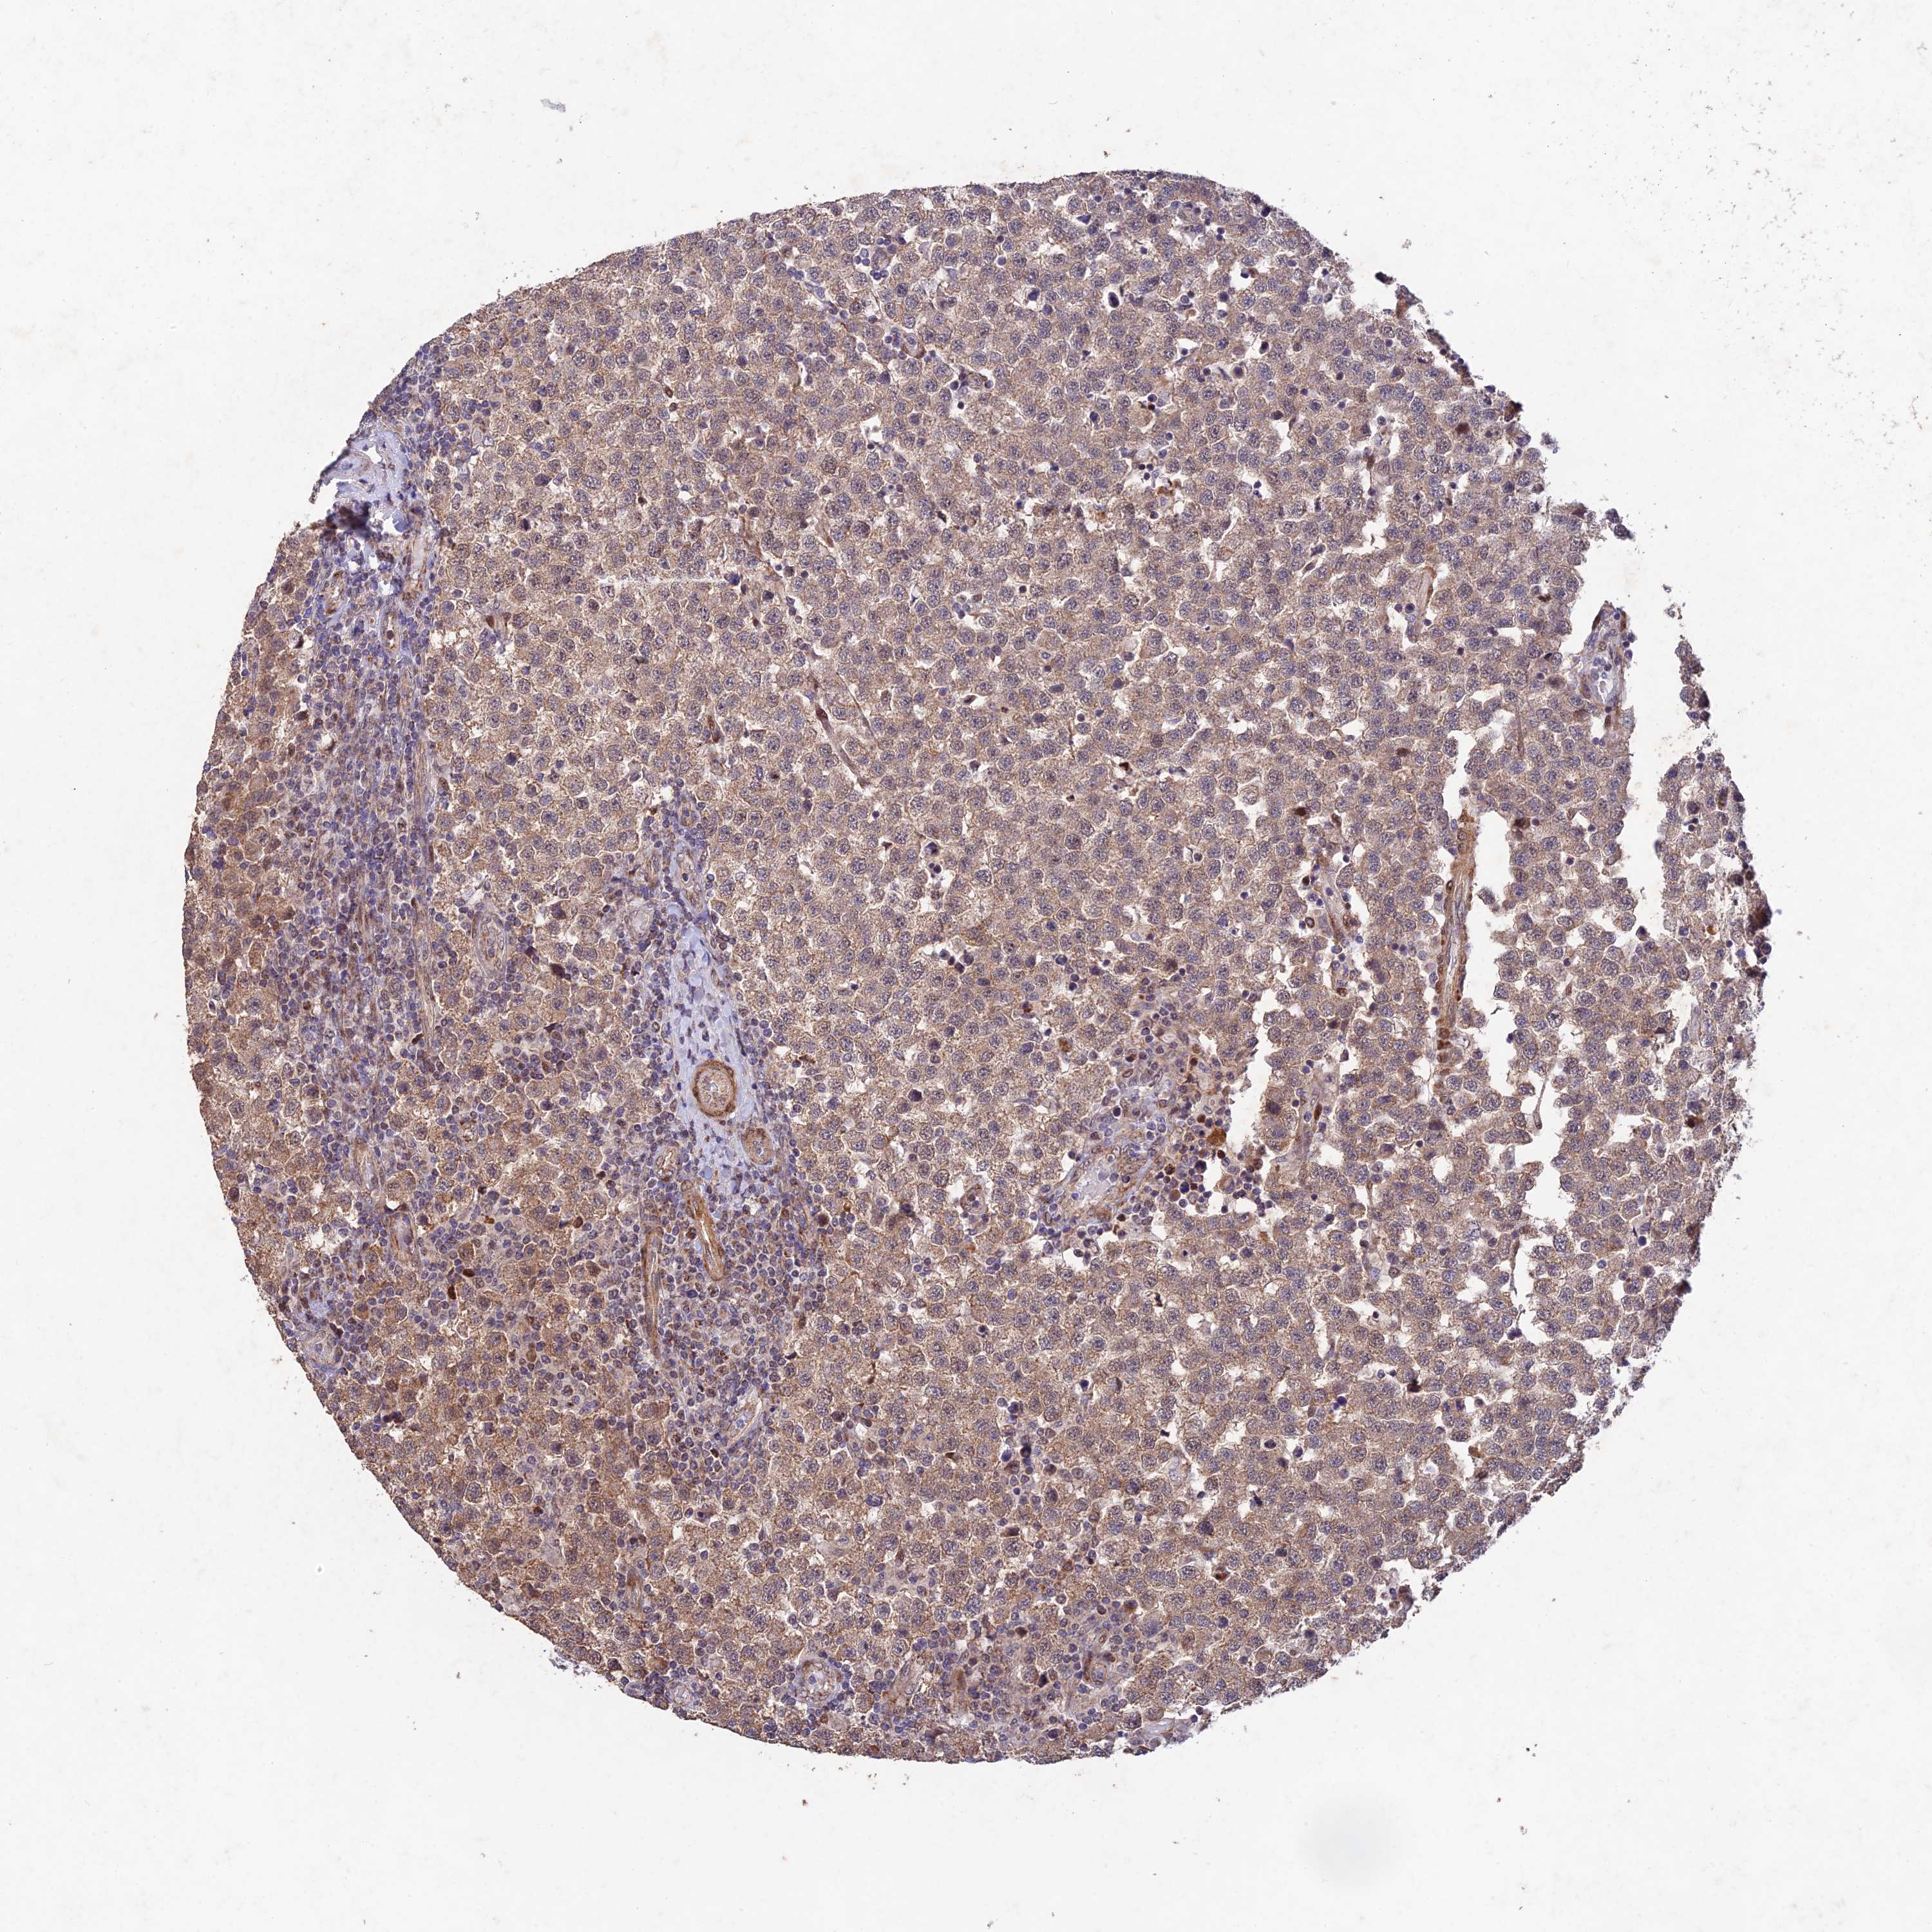

TESTIS CANCER - Protein expressioni

A mouse-over function shows sample information and annotation data. Click on an image to view it in a full screen mode. Samples can be filtered based on level of antibody staining by selecting one or several of the following categories: high, medium, low and not detected. The assay and annotation is described here.

Note that samples used for immunohistochemistry by the Human Protein Atlas do not correspond to samples in the TCGA dataset.

Antibody stainingi

Antibody staining in the annotated cell types in the current human tissue is reported as not detected, low, medium, or high, based on conventional immunohistochemistry profiling in selected tissues. This score is based on the combination of the staining intensity and fraction of stained cells.

Each image is clickable and will lead to virtual microscopy that enables deeper exploration of all samples and also displays staining intensity scores, fraction scores and subcellular localization as well as patient and tissue information for each sample.

Antibody HPA043470

Antibody HPA048143

Staining

High

Medium

Low

Not detected

Intensity

Strong

Moderate

Weak

Negative

Quantity

>75%

75%-25%

<25%

None

Location

Nuclear

Cytoplasmic/membranous

Cytoplasmic/membranous,nuclear

Carcinoma, Embryonal, NOS

Seminoma, NOS